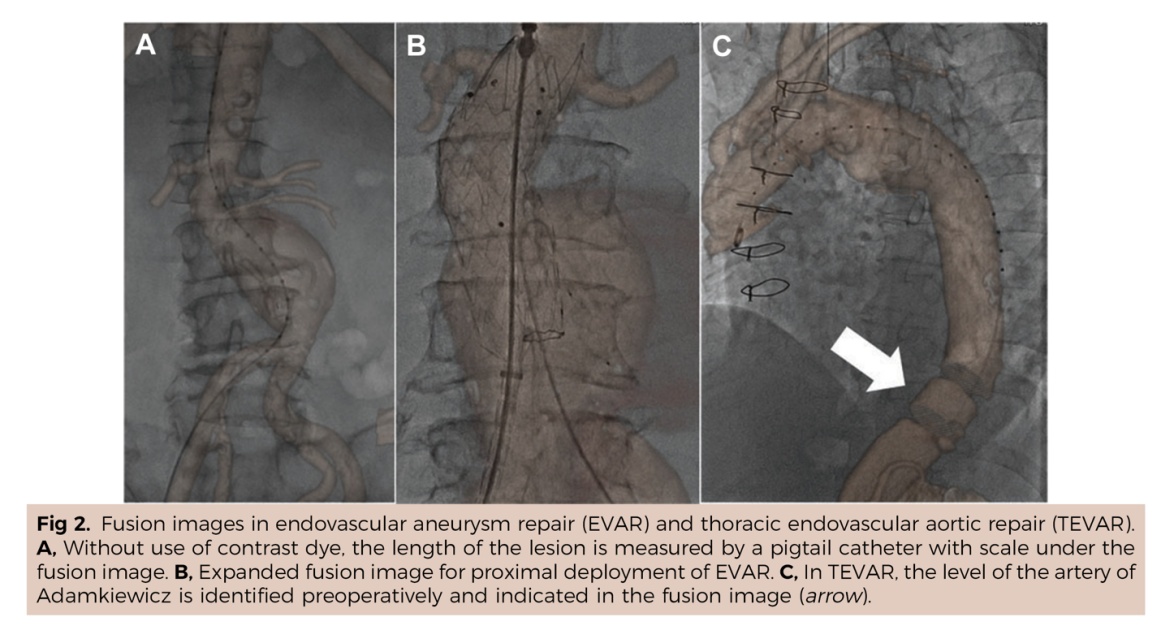

为减少手术中造影剂使用量和辐射线照耀剂量,术中图像会通、路图等导航软件应时而生。尽管当今已有国际厂商推出搭载新式图像会通系统的新建立亚洲色图,但仍存在问题。

国际报说念的DSA术中图像会通技能,会通图像隐晦不清,CTA图像为3D重建影像,DSA为2D影像,两者图层之间浅薄类似障翳,了了度彰着受到互相影响。

禄韶英教师团队与北京飞燕四海医疗科技公司的工程师联袂谐和,纠合当今开首进的图像分割、及时标注算法,研发出了基于神经网罗、AI深度学习的DSA术中及时导航软件“AngiSight”。该软件杀青了三大技能冲突:在体位固定下达到0.1毫米级血管概括识别的精确导航,床位变动后3-5秒内完成新图像会通的及时反应,以及无需建立硬件升级即可适配各品牌DSA机型的平庸兼容性。运用该系统对52例临床真正病例进行回来性扣问恶果证实,不仅斥责了40%的辐射认知,单次手术精真金不怕火60%造影剂,还使急诊手术时期裁减了35%,为抢救赢得了黄金窗口,同期提升了慢性血管阻塞等疑难病例15%的收效能。